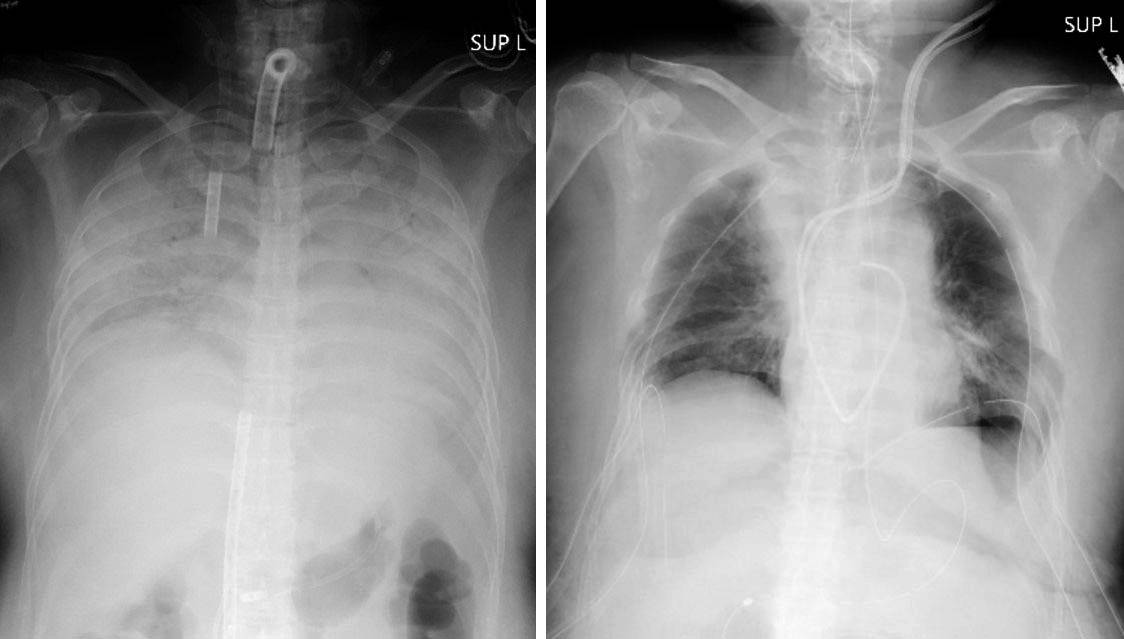

แต่ในเคสนี้เกิดขึ้นกับคนไข้หญิงที่ติดเชื้อโควิด ซึ่งแพทย์วินิจฉัยแล้วว่าปอดของเธอไม่สามารถฟื้นฟูให้กลับมาเป็นสภาพเดิมได้ ตอนนี้ทางโรงพยาบาลได้ใช้ปอดเทียม ทางออกเดียวคือการปลูกถ่ายปอดที่จะช่วยชีวิตเธอได้ ทางสามีและลูกชายของเธอจึงตัดสินใจบริจาคปอดให้ซึ่งทางแพทย์แจ้งว่านั่นอาจทำให้การทำงานของปอดลดประสิทธิภาพลดลง

การผ่าตัดในครั้งในใช้เวลายาวนานถึง 11 ชั่วโมง เริ่มตั้งแต่การผ่าตัดย้ายปอดจากผู้บริจาคที่เป็นสามีและลูกชายของคนไข้ เพื่อทดแทนปอดที่เสียหายจากการติดเชื้อโควิด ร่างกายของผู้บริจาคทั้สองคนอยู่ในสภาพปกติ ส่วนคนไข้นั้นอยู่ในห้อง ICU ถ้าหากการผ่าตัดเป็นไปได้ด้วยดี คาดว่าทั้งผู้ป่วยและผู้บริจาคจะฟื้นตัวได้ในเวลา 2 เดือน